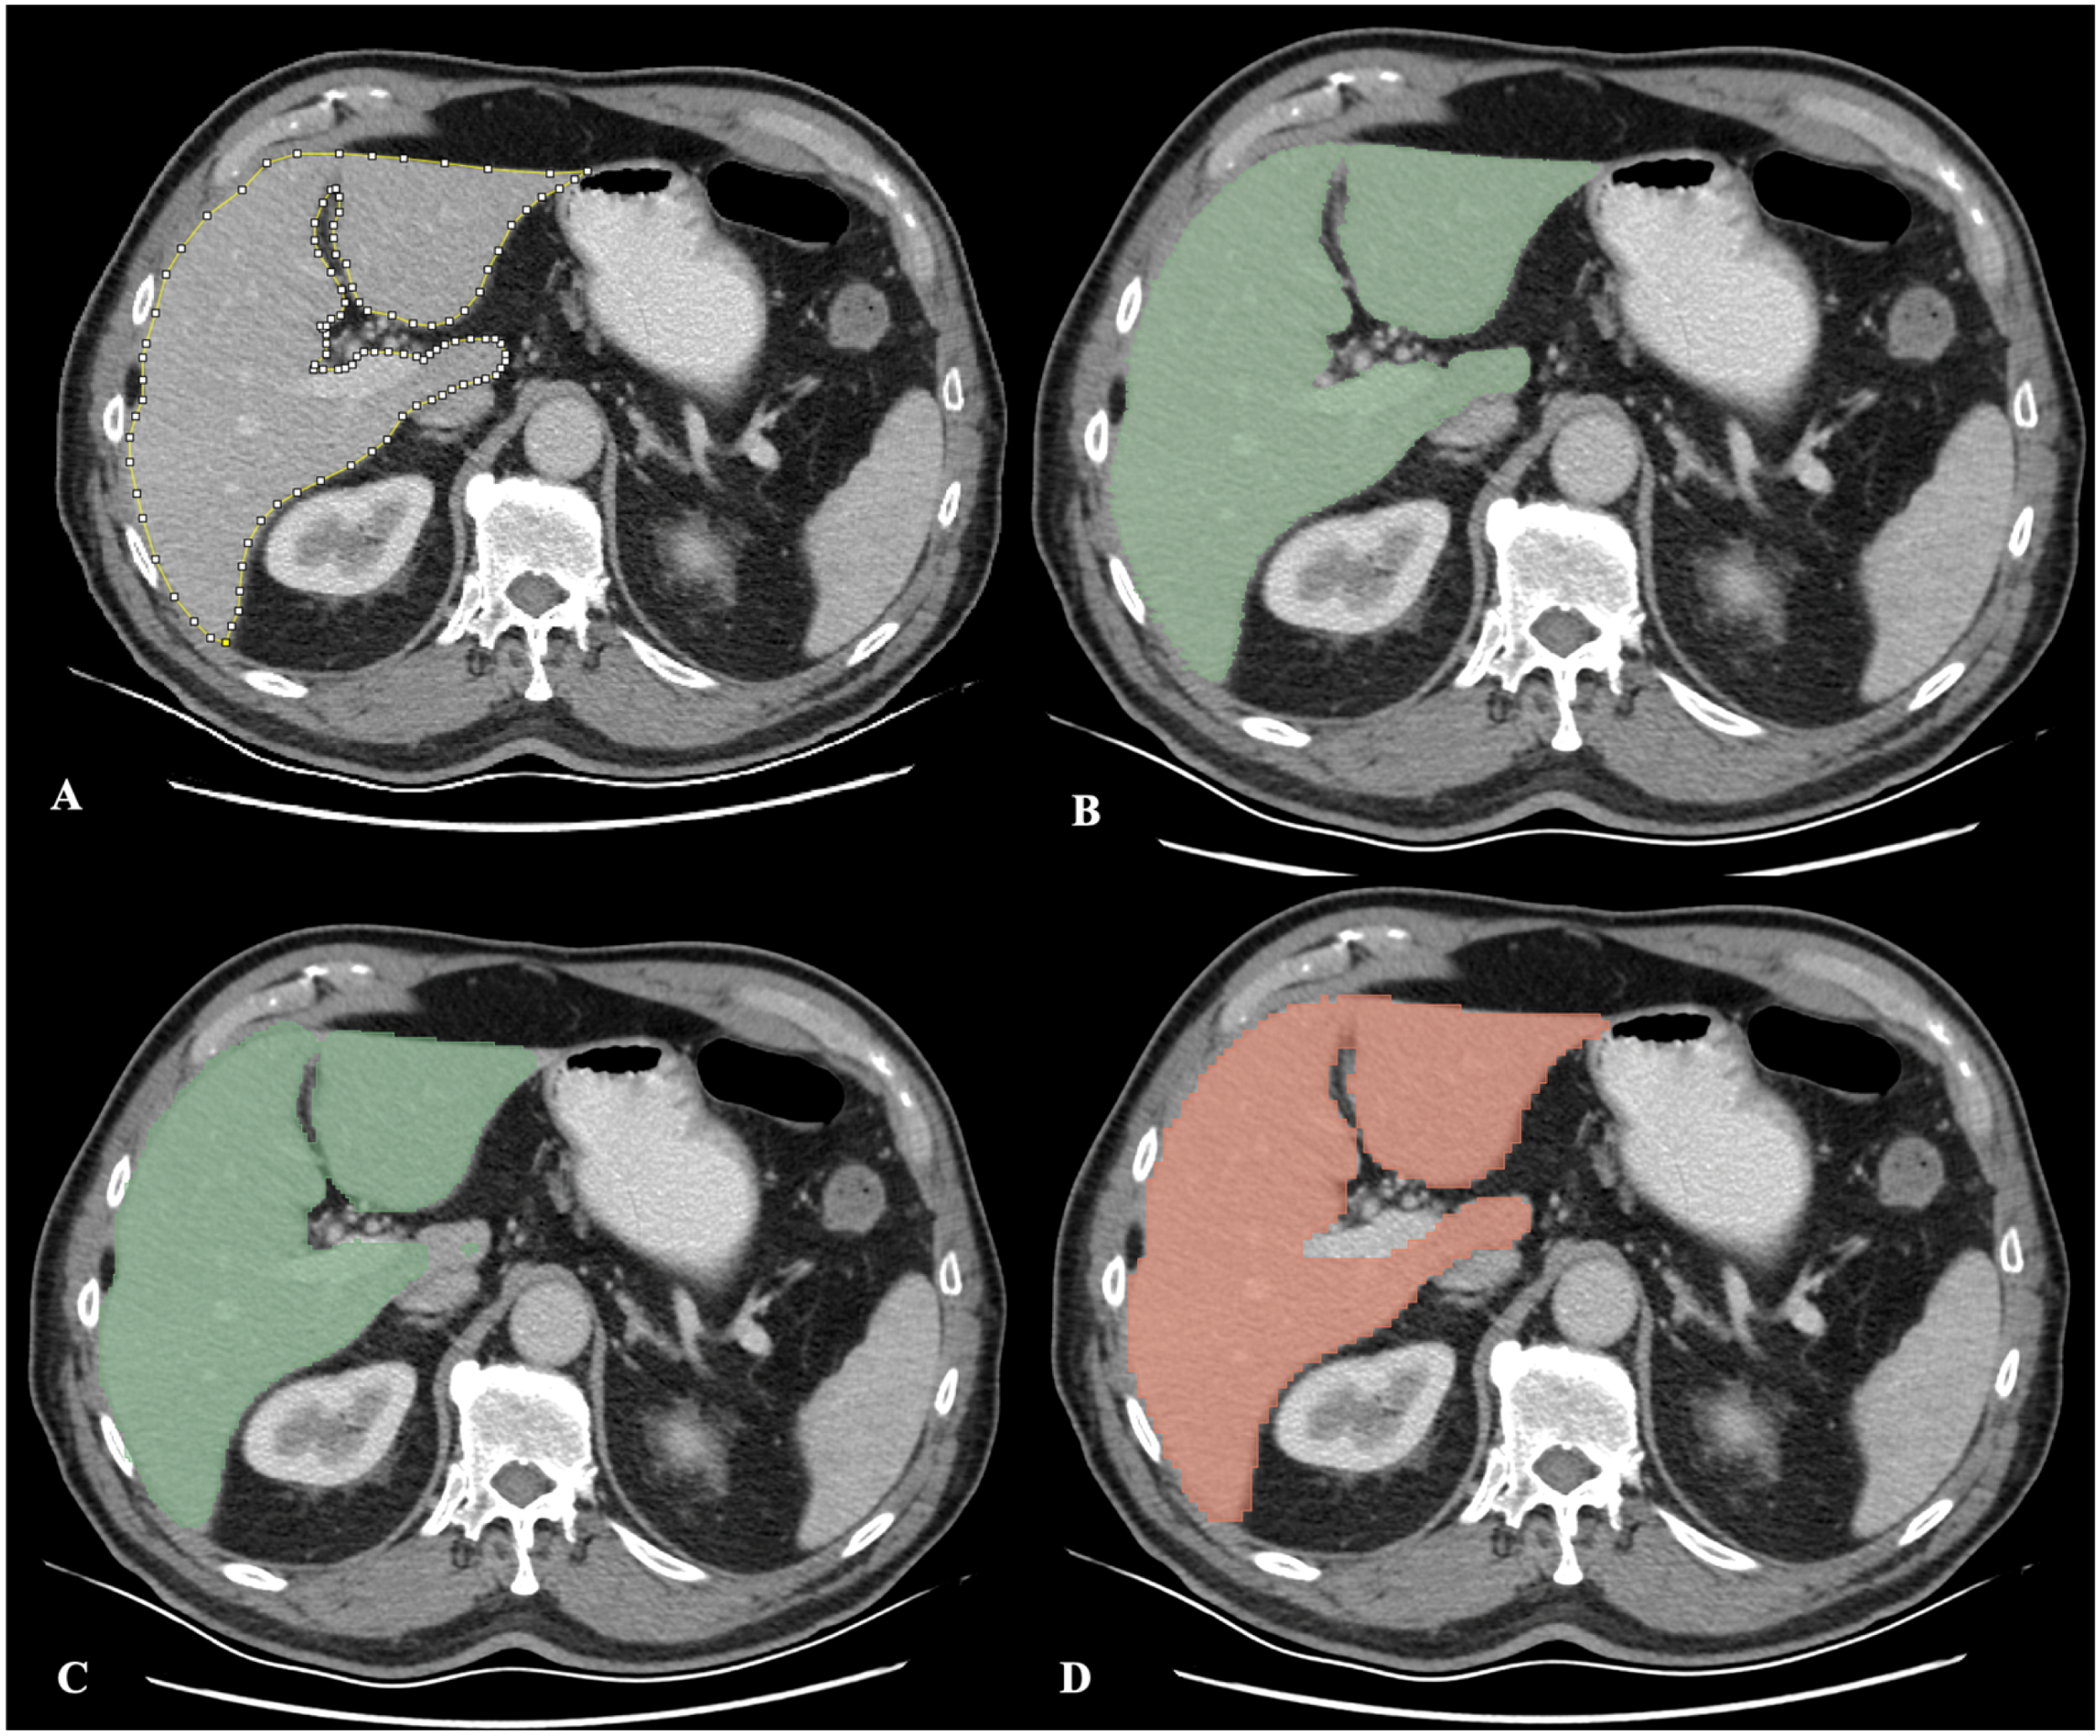

2.3.1. Manual Segmentation

2.3.2. Semi-Automatic Segmentation with the RVX Liver Module

2.3.3. Deep Learning-Based Segmentation with the RVX Liver Module

2.3.4. Automatic Segmentation with the TotalSegmentator Module